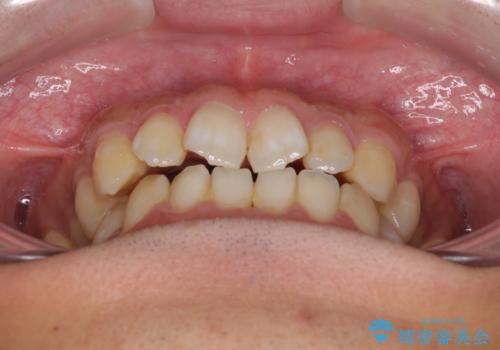

下顎前歯と上顎の部分矯正

- 上下の前歯の叢生を気にして来院された患者様です。

前歯のみの矯正治療を希望でしたが、上顎臼歯が舌側転位していたため、上顎は全体を、下顎は前歯のみを矯正治療することとしました。